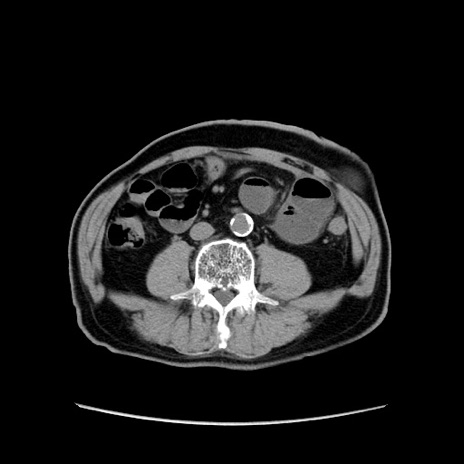

症例24(横断像)

【症例】80歳代男性

【主訴】左側腹部痛、嘔吐

【現病歴】本日早朝より左腹部に痛みあり。昼頃嘔吐認めたため、救急要請。

【既往歴】直腸癌(Mile手術)、胆摘

【身体所見】意識清明、BT 35.9℃、BP 221/93mmHg、SpO2 97%(RA) 、腹部:左ストーマ周囲に限局性の腹部膨隆あり。 膨隆部自発痛・圧痛あり・軟。

【データ】WBC 7700、CRP 0.09